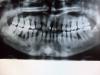

denki Опубликовано 14 апреля, 2009 Поделиться Опубликовано 14 апреля, 2009 Здравствуйте!Месяц назад отправил жену на консультацию к стоматологу в ЦНИИС - наговорили столько просто ужас. Диагноз - генерализованный пародонтит.А тут оказалась беременность 1,5 месяца, прочитала в инете и ужаснулась, что поздно. Что посоветуйте чтоб сохранить зубы и как дальше действовать? Как это может отразиться на ребенке? Хочется здорового ребенка и здоровую жену!В прикрепленном файле снимок.Заранее спасибо за рекомендацию. Ссылка на комментарий

доминика Опубликовано 15 апреля, 2009 Поделиться Опубликовано 15 апреля, 2009 Здравствуйте!Месяц назад отправил жену на консультацию к стоматологу в ЦНИИС - наговорили столько просто ужас. Диагноз - генерализованный пародонтит.А тут оказалась беременность 1,5 месяца, прочитала в инете и ужаснулась, что поздно. Что посоветуйте чтоб сохранить зубы и как дальше действовать? Как это может отразиться на ребенке? Хочется здорового ребенка и здоровую жену!В прикрепленном файле снимок.Заранее спасибо за рекомендацию.качество опг плохое ,темное очень ,сфотографируйте на светлом экране компьютера ,не видно ничего Ссылка на комментарий

denki Опубликовано 17 апреля, 2009 Автор Поделиться Опубликовано 17 апреля, 2009 Добрый день!Во вложении снимок более яркий. В институте говорили, подразумевая что нет беременности.А она сейчас есть и насторожило предложение вести лечение не через кассу. Ссылка на комментарий

Д.С. Опубликовано 17 апреля, 2009 Поделиться Опубликовано 17 апреля, 2009 Добрый день!Во вложении снимок более яркий. В институте говорили, подразумевая что нет беременности.А она сейчас есть и насторожило предложение вести лечение не через кассу.Как минимум с половиной зубов Вам придется расстаться. Ссылка на комментарий

доминика Опубликовано 17 апреля, 2009 Поделиться Опубликовано 17 апреля, 2009 ситуация действительно очень тяжелая ищите хорошего пародонтолога ,не все зубы спасете Но попытаться можно ,уже необходимо проведение лоскутных операций с применением остеопластических материалов и мембран плюс антибиотикотерапия ,в первом триместре беременности этого делать нельзя,в тоже время такое состояние -это большой очаг хронической инфекции...ситуация не из простых Ссылка на комментарий

Bier Опубликовано 19 апреля, 2009 Поделиться Опубликовано 19 апреля, 2009 все зубы верхней челюсти придется удалить. Это единственная возможность сохранить оставшуюся кость, которую можно будет использовать для имплантации. Часть зубов на н.челюсти тоже надо удалить. Но тут большую часть можно сохранить. Ссылка на комментарий

доминика Опубликовано 30 апреля, 2009 Поделиться Опубликовано 30 апреля, 2009 Здравствуйте. Генерализованный пародонтит на будущем ребенке он не отразится. Но это заболевание может усугубиться беременностью. К сожалению, качество снимка не дает возможности оценить убыль костной ткани во фронтальном отделе. На сроке с 3-го по 7-ой мес. можно провести терапевтические мероприятия для стабилизации процесса.вы пошутили я надеюсь ,разверните две ладони -по обьему воспаленный пародонт как раз равен этой площади ,а теперь представим что две ладошки воспалены и в гною -генерализ.хрон.пародонтит-это серьезный удар по иммунной системе ,и только терапевтическими мероприятиями здесь не обойтись ,не нужно дезинформировать пациента Ссылка на комментарий